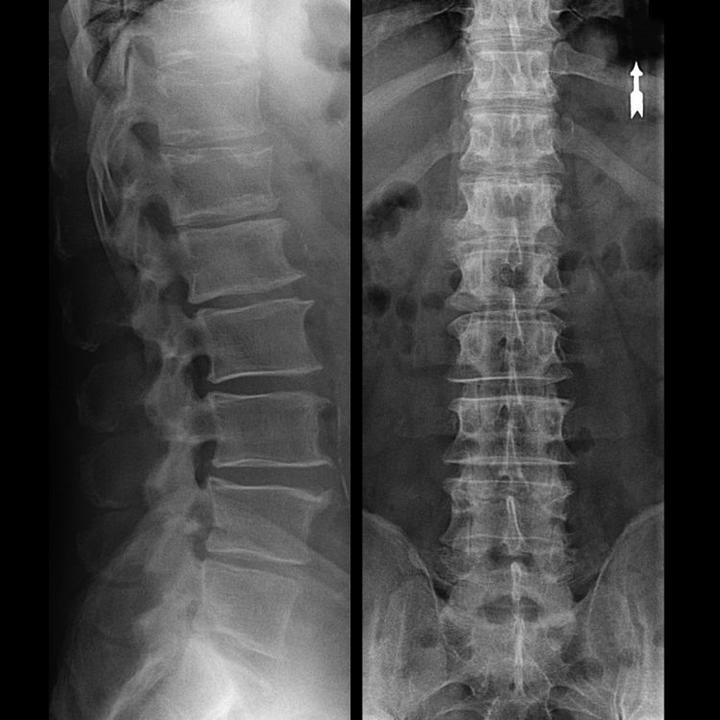

With the help of the tests for the bending of the spine is determined by the amplitude of movements of the patient. Through the use of the x-ray, CT and MRI, the diagnosis was the largest pour in the concrete is defined l and future strategy for the treatment of osteochondrosis.

S sets The diagnosis on admission by a neurologist based on the patient's complaints (pain, limitation of mobility, etc.). They inspect the spine with the patient standing, sitting and lying (en en rest and movement). In the inspection of the back draws attention to your posture, characteristics of The structure of the body of the corners of the leaves lower, side, the contours of the neck and the waist, the position of the shoulder girdle, etc. then the doctor usually the patient is referred to the two rays x, CT or MRI, I clarifies that produces the diagnosis, and determined by the degree of damage, and identify deviations and hidden from the norm. These data According to the neurologist assigned the appropriate treatment. Typically, this, a un complex therapy, including the use of drugs, massage, physical therapy and other methods.